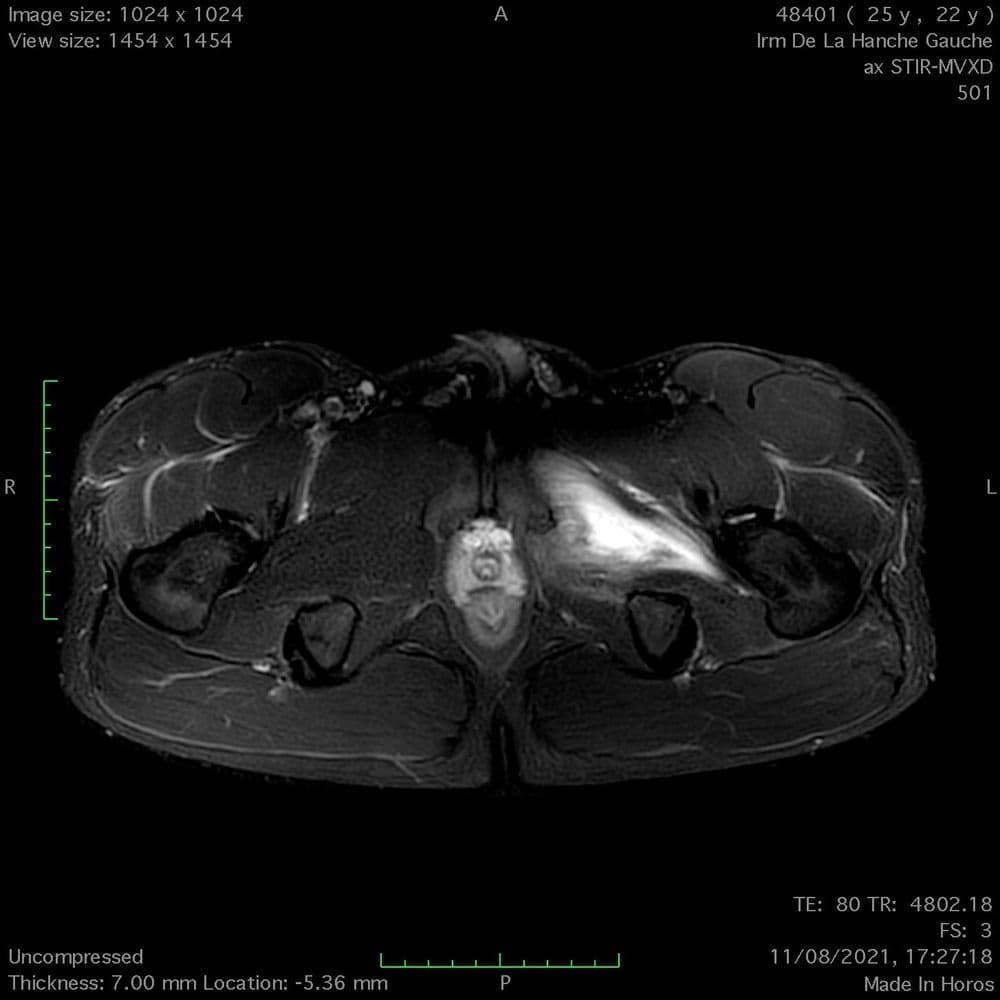

Douleur inguinale sur une passe plat du pied contrée en jouant au football

MRI

Lésion myotendineuse de grade 3b (BAMIC) du grand adducteur